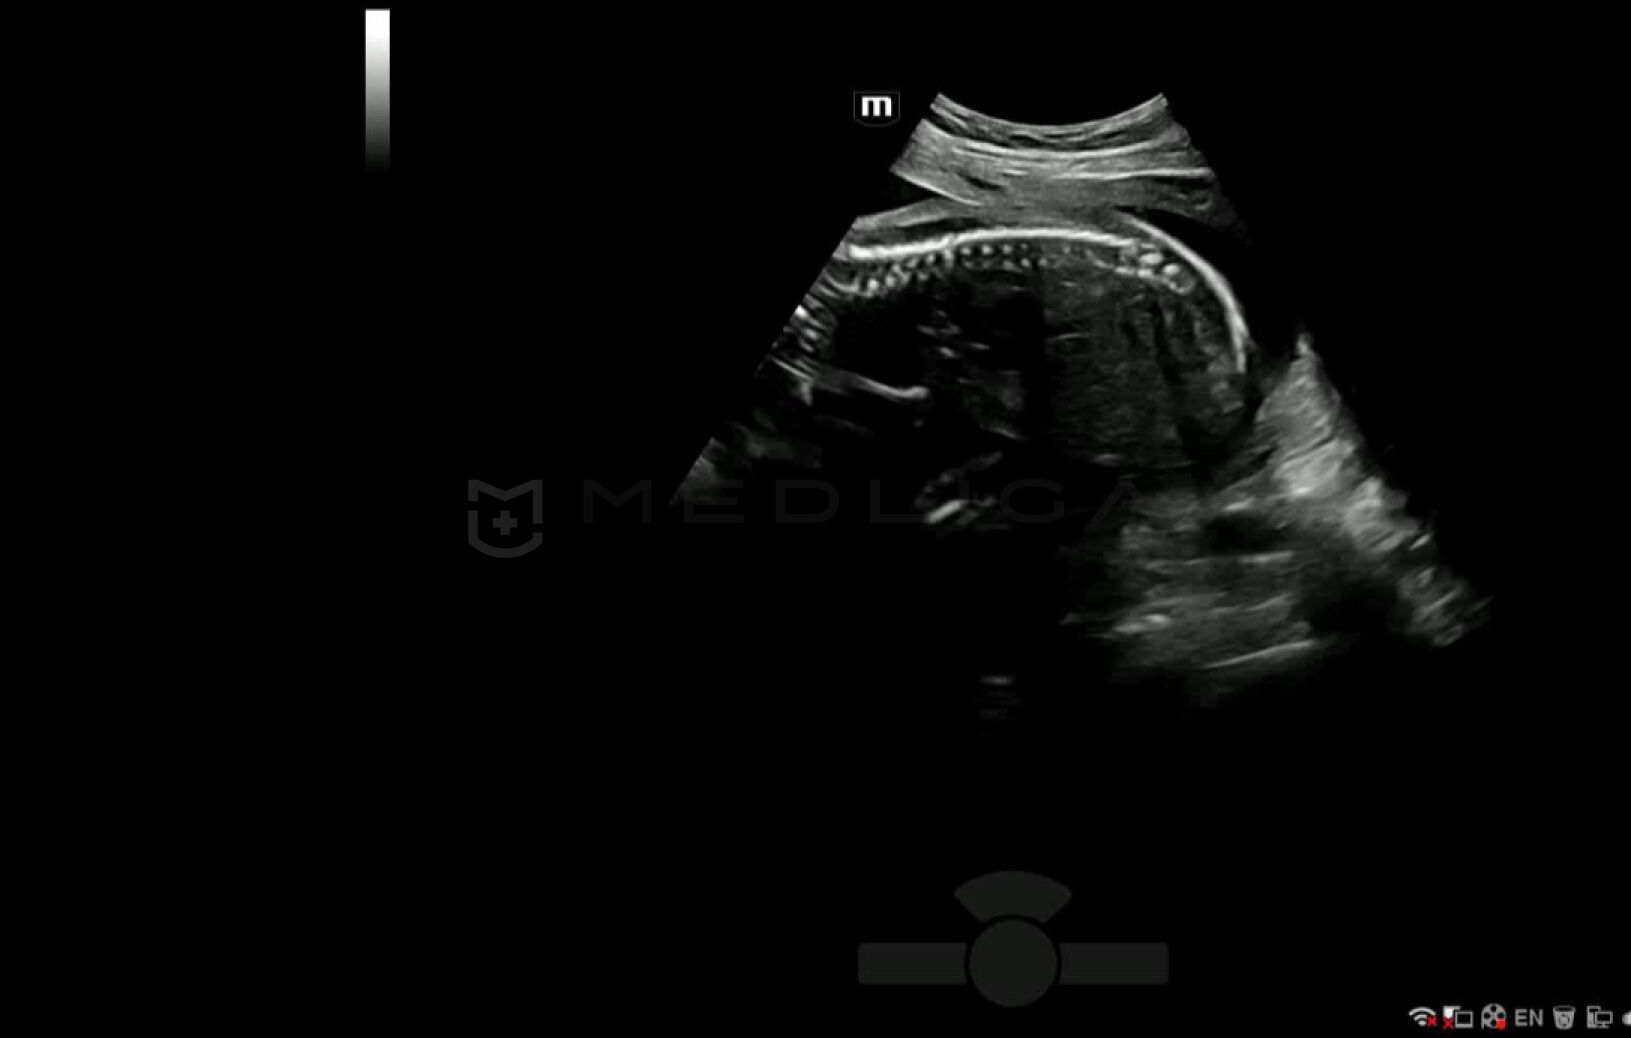

С легкостью получайте потрясающие 3D изображения позвоночника плода

- Автоматическое распознавание анатомии позвоночника плода

- Автоматическая подстройка зоны интереса и положения до оптимального

- Автоматический определение параметров рендеринга позвоночника